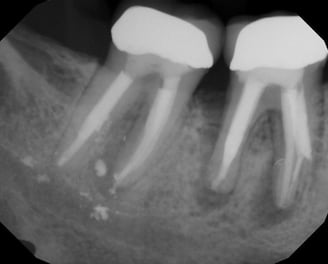

Diagnóstico de dolor dental

Consiste en identificar la causa del dolor en un diente, ya sea por caries, infecciones u otras afecciones. Se realiza mediante exámenes clínicos, radiografías y pruebas de sensibilidad.

Evaluación de la vitalidad dental

Se determina si la pulpa del diente (el tejido interno) está viva o muerta. Esto se realiza mediante pruebas de sensibilidad térmica o eléctrica para evaluar la respuesta del diente.

Se identifica si hay fracturas en la raíz del diente, que pueden causar dolor, infecciones o problemas de estabilidad dental. Se utilizan radiografías y exámenes clínicos para este diagnóstico.

Evaluación de fracturas radiculares

Se analiza el estado de dientes que han recibido tratamientos endodónticos anteriores para verificar su éxito y determinar si se necesita un retratamiento.

Evaluación de dientes con tratamientos previos